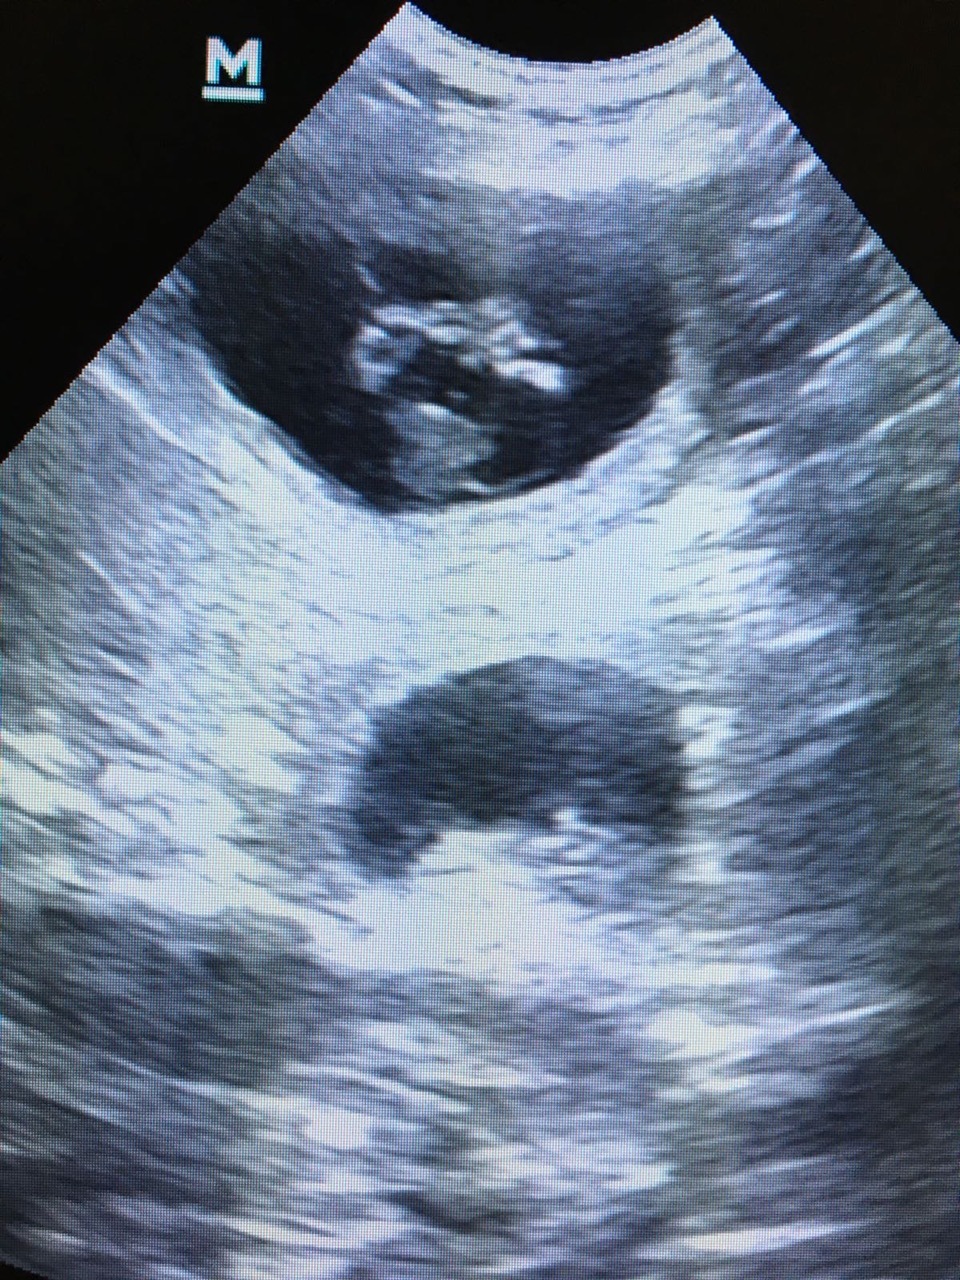

Die Untersuchungen Nalas per Ultraschall und Röntgen ergaben keine pathologischen (krankhaften) Befunde. Bei der Blutuntersuchung wurden eine leichte Anämie (Blutarmut) und ein deutlicher Hinweis auf eine bakterielle Infektion festgestellt. Nach entsprechender medikamenteller Behandlung mit Dauertropfinfusion wurde ein Welpe geboren. Trotz sich anschließender Arzneimittelgaben konnte keine weitere Spontangeburt ausgelöst werden.

In Absprache mit den Besitzern entschied ich mich für einen Kaiserschnitt, um eine gute Überlebenschance der noch nicht geborenen Welpen zu erhalten. Aufgrund der fortgeschrittenen Zeit, mittlerweile war es Mitternacht, und der Notbesetzung des OP-Teams wurden die Tierbesitzer in die Versorgung der Welpen mit einbezogen. Umgehend war Nala für die Operation vorbereitet und narkotisiert. Fünf weitere Welpen konnten lebend entwickelt werden. Leider waren zwei Welpen bereits im Mutterleib verstorben.